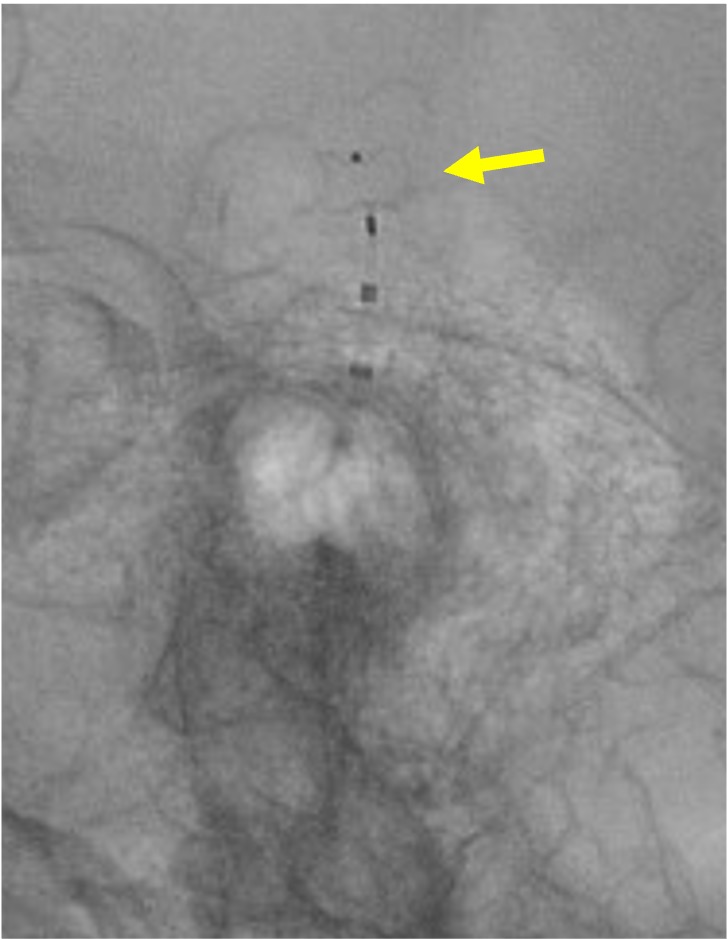

当院で行われた症例を提示いたします。80歳、女性、くも膜下出血の患者様。血管撮影にて図1〜4赤矢印の様に脳底動脈に広頸のネックを伴う不整形の瘤を認めました。母血管の蛇行狭窄が強く、マイクロカテーテルが複数入りにくい状態だったのでWEB(図5〜8黄色矢印)を用いて治療を行いました。術後MRAでも図10青矢印の様に動脈瘤は描出されません(図9は術前MRA)。現在も出血なく経過しております。

図7 |